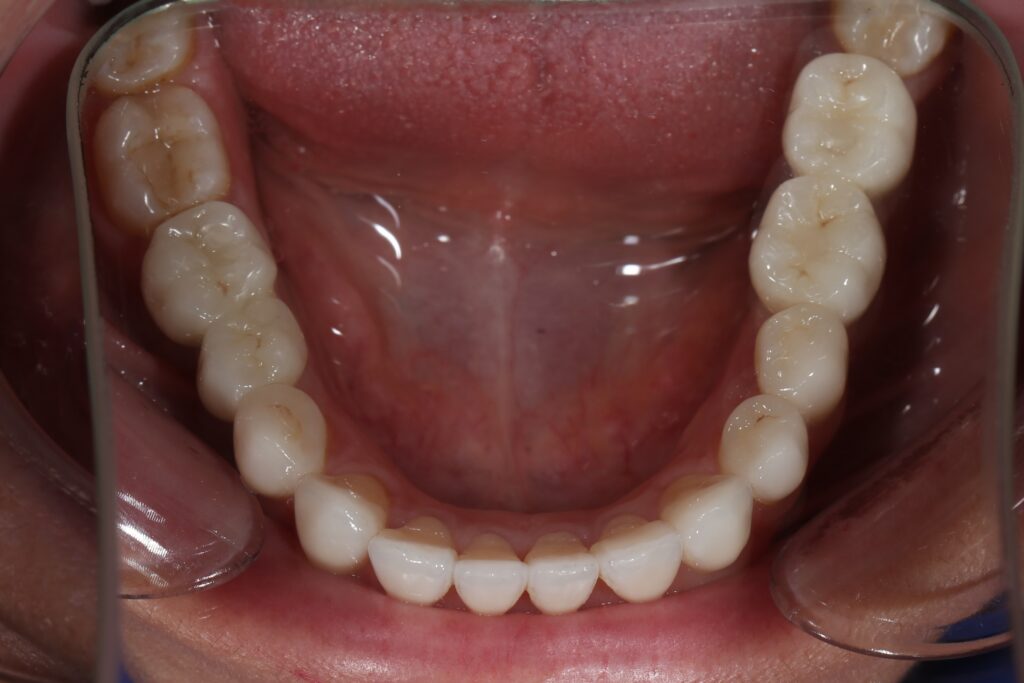

Результаты ортодонтической части

Была установлена брекет-система Damon Q. Срок лечения брекетами составил 11 месяцев.